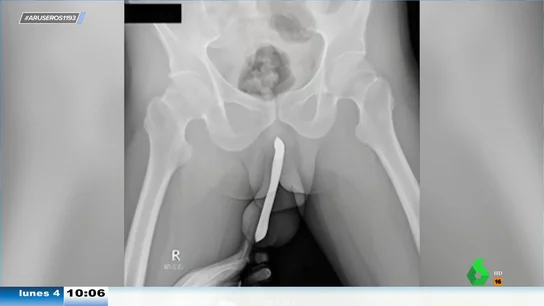

Las imágenes no son aptas para personas sensibles